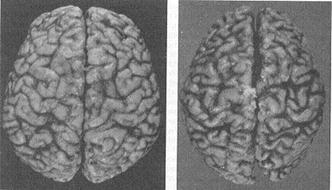

Il cervello di un individuo affetto da Alzheimer appare come un pallone sgonfio a causa della continua eliminazione di neuroni. A sinistra c'è un cervello sano, a destra uno malato.

È assolutamente evidente dalle foto precedenti quanto sia dannoso ed ingente il danno che l'Alzheimer reca al tessuto nervoso: il cervello si sgretola, perde di consistenza accartocciandosi su se stesso. Fu proprio questa la visione che portò il dottor Alzheimer a descrivere il cervello malato dicendo che «presentava una scarsità di cellule nella corteccia cerebrale». Inoltre, le cellule rimaste vengono saturate di placche senili di β-amiloide, rendendo complicati i trasferimenti degli impulsi da una parte all'altra del sistema nervoso. Queste placche sono quelle che Alzheimer definì nell'autopsia di Auguste come «gruppi di filamenti localizzati fra le cellule nervose».